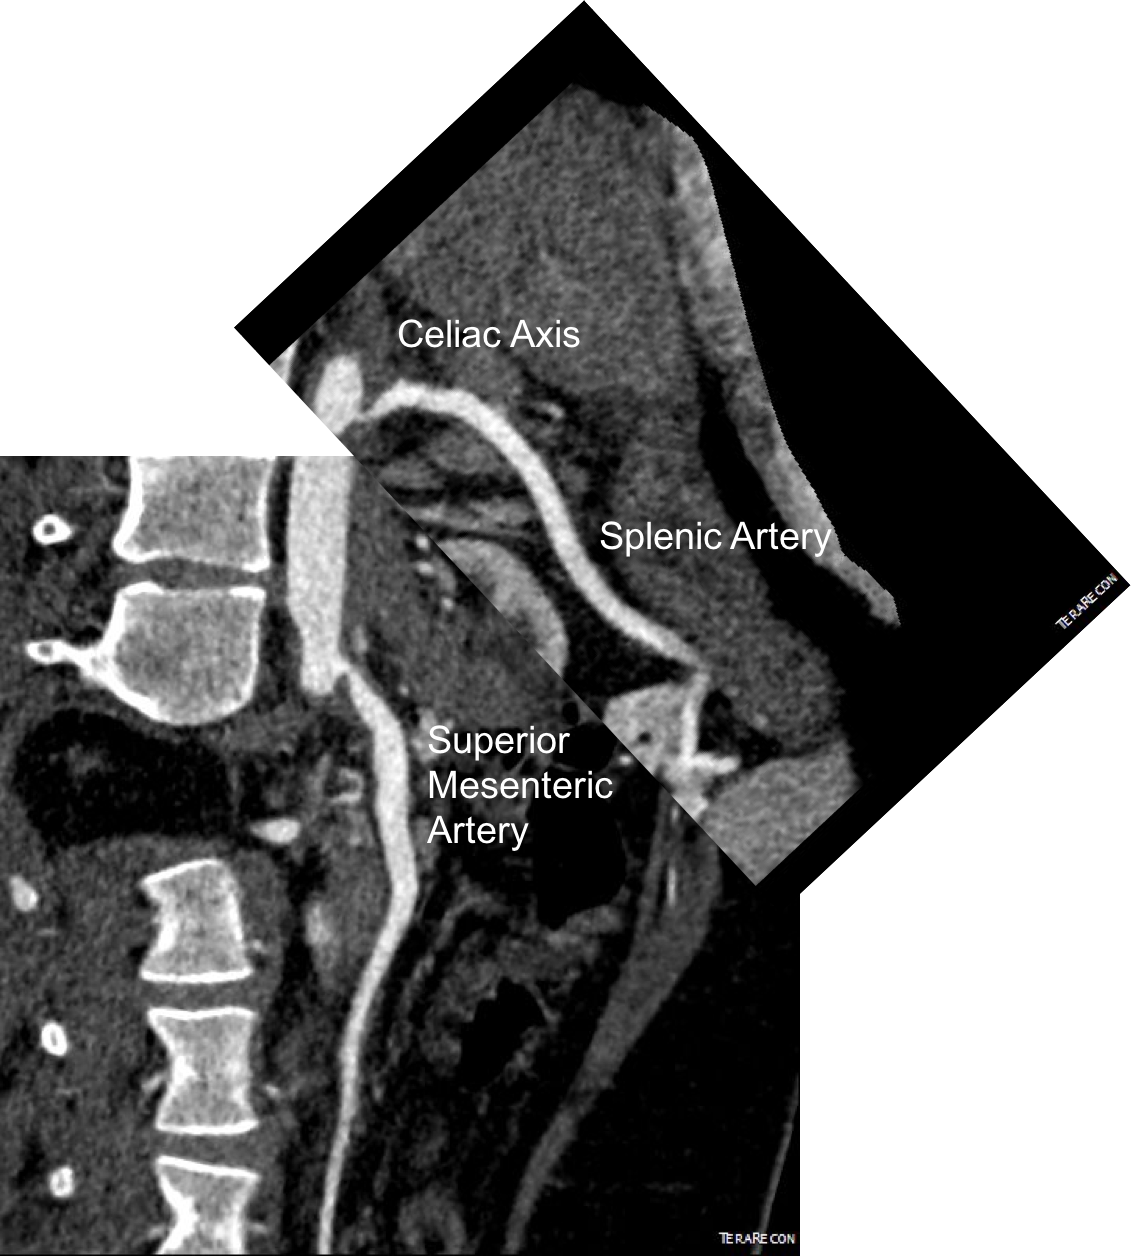

Examination was remarkable for a well nourished young woman in distress with epigastric tenderness. Inflammatory markers were normal and she was on methotrexate and tocilizumab. CTA (above) and duplex showed severe stenoses affecting the origins of the celiac axis and superior mesenteric artery. A composite of the centerlines through these showed the arteries to be critically narrowed at their origins (below), along with a mild to moderate stenosis of the aorta (above). No active inflammation could be seen.

precenterlineCA and SMA.png

I did feel that revascularizing the SMA was likely to improve her postprandial symptoms, given the paucity of circulation to the gut. I had a discussion about her chest pain and the thought that this was a celiac plexus neuropathy as the result of compression of the celiac plexus by her Takayasu’s disease. Typically, for younger people, I perform a bifurcated graft to the celiac axis and SMA from the distal descending thoracic aorta for younger patients, but I had no intention of replacing her aorta at this time, and wanted to reserve any definitive revascularization of her visceral vessels for a later time if it became necessary. Her pulses were full in the legs and she had no hypertension, renal insufficiency, or claudication. I therefore planned a ilio-mesenteric bypass, as it would preserve planes for a later more definitive operation if necessary, and would address her mesenteric ischemia.